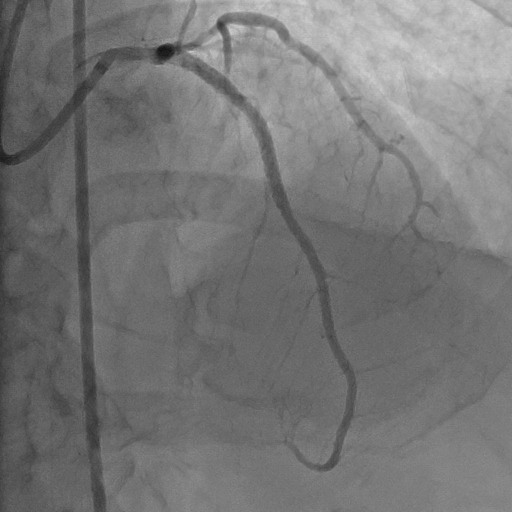

Hình ảnh động mạch chủ sau phẩu thuật.

Để cứu sống bệnh nhân trong thời gian khẩn cấp, các bác sĩ tim mạch can thiệp đã tiến hành đặt stent trên đoạn mạch vành bị tắc. Stent mạch vành là những khung lưới kim loại nhỏ đặt trong lòng mạch vành nhằm mở rộng vị trí lòng mạch bị hẹp và ngăn không cho nó bị hẹp trở lại. Sau can thiệp bệnh nhân hoàn toàn tỉnh táo, triệu chứng đau ngực đã giảm, các dấu hiệu sinh tồn trở về mức ổn định.